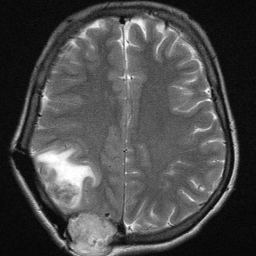

Figure 1: Heatmap Comparison of Unhealthy Images. Different columns show unhealthy MRI images of different positions, sizes, and textures. The first row is the raw image. The second row is the heatmap predicted with PatchCore. The third raw is the heatmap predicted with the proposed method.